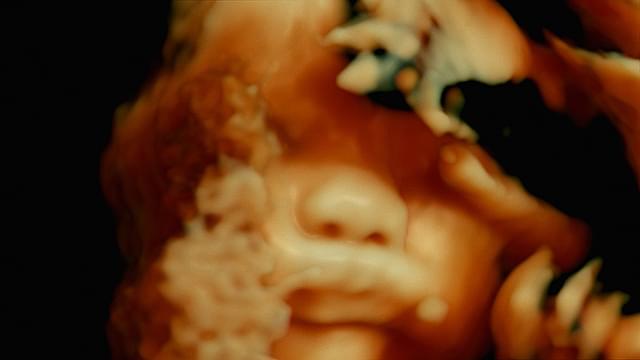

パリ北部近郊の5つの病院のオペ室を舞台に、普段は決して見ることのできない手術時の医師視点のカメラや内視鏡カメラなどの映像を使用しながら、脳や大腸、眼球、男性器などさまざまな外科手術や帝王切開の模様を映しだす。さらに、死と隣りあわせの職場で働く医療従事者たちの心境や、死体安置所での「おくりびと」たちの仕事ぶりをとらえ、医療とは何か、そして肉体と魂とは何かという疑問を探る。